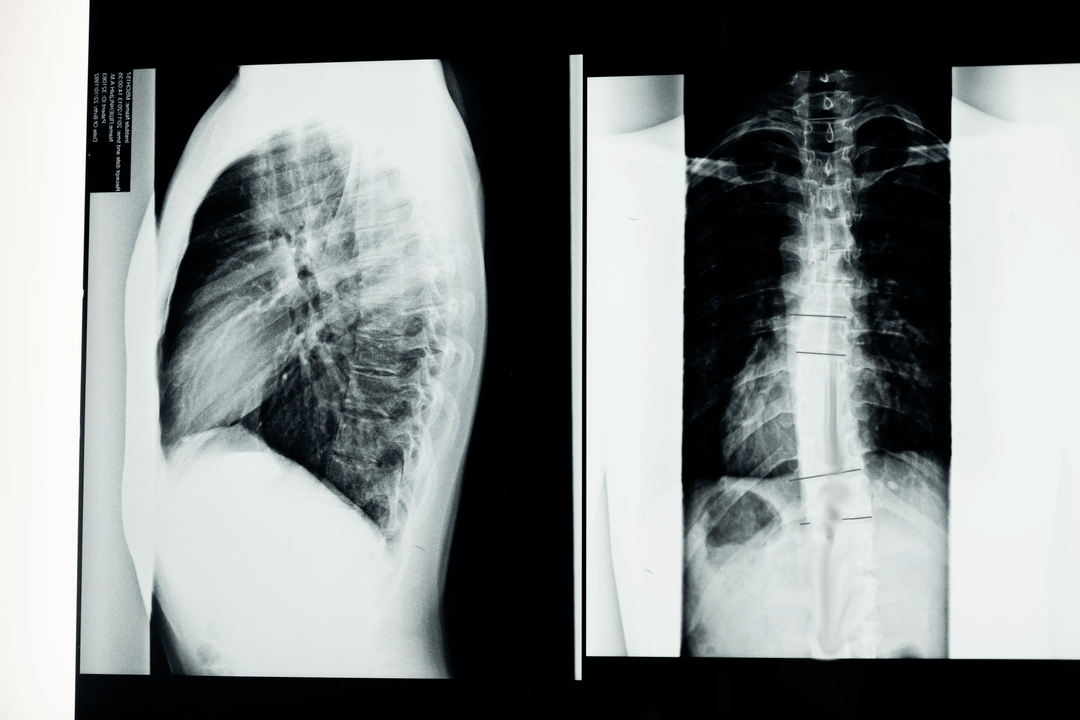

Before starting diagnostic studies, the neurologist collects the patient's medical history and carefully studies his complaints.Osteochondrosis has common symptoms with some other diseases, so it is important to know how to distinguish pathologies.X-ray studies will help confirm the diagnosis of osteochondrosis: radiography, myelography and computed tomography.

An X-ray allows you to get an X-ray image of the spine or part of it.In this way, the doctor can determine the place affected by the disease.For the sake of clarity, we will explain how osteochondrosis can be determined by an X-ray: the image will show a narrowing of the intervertebral disc, the presence of bone growths (osteophytes) or a change in the shape of a spinal segment.